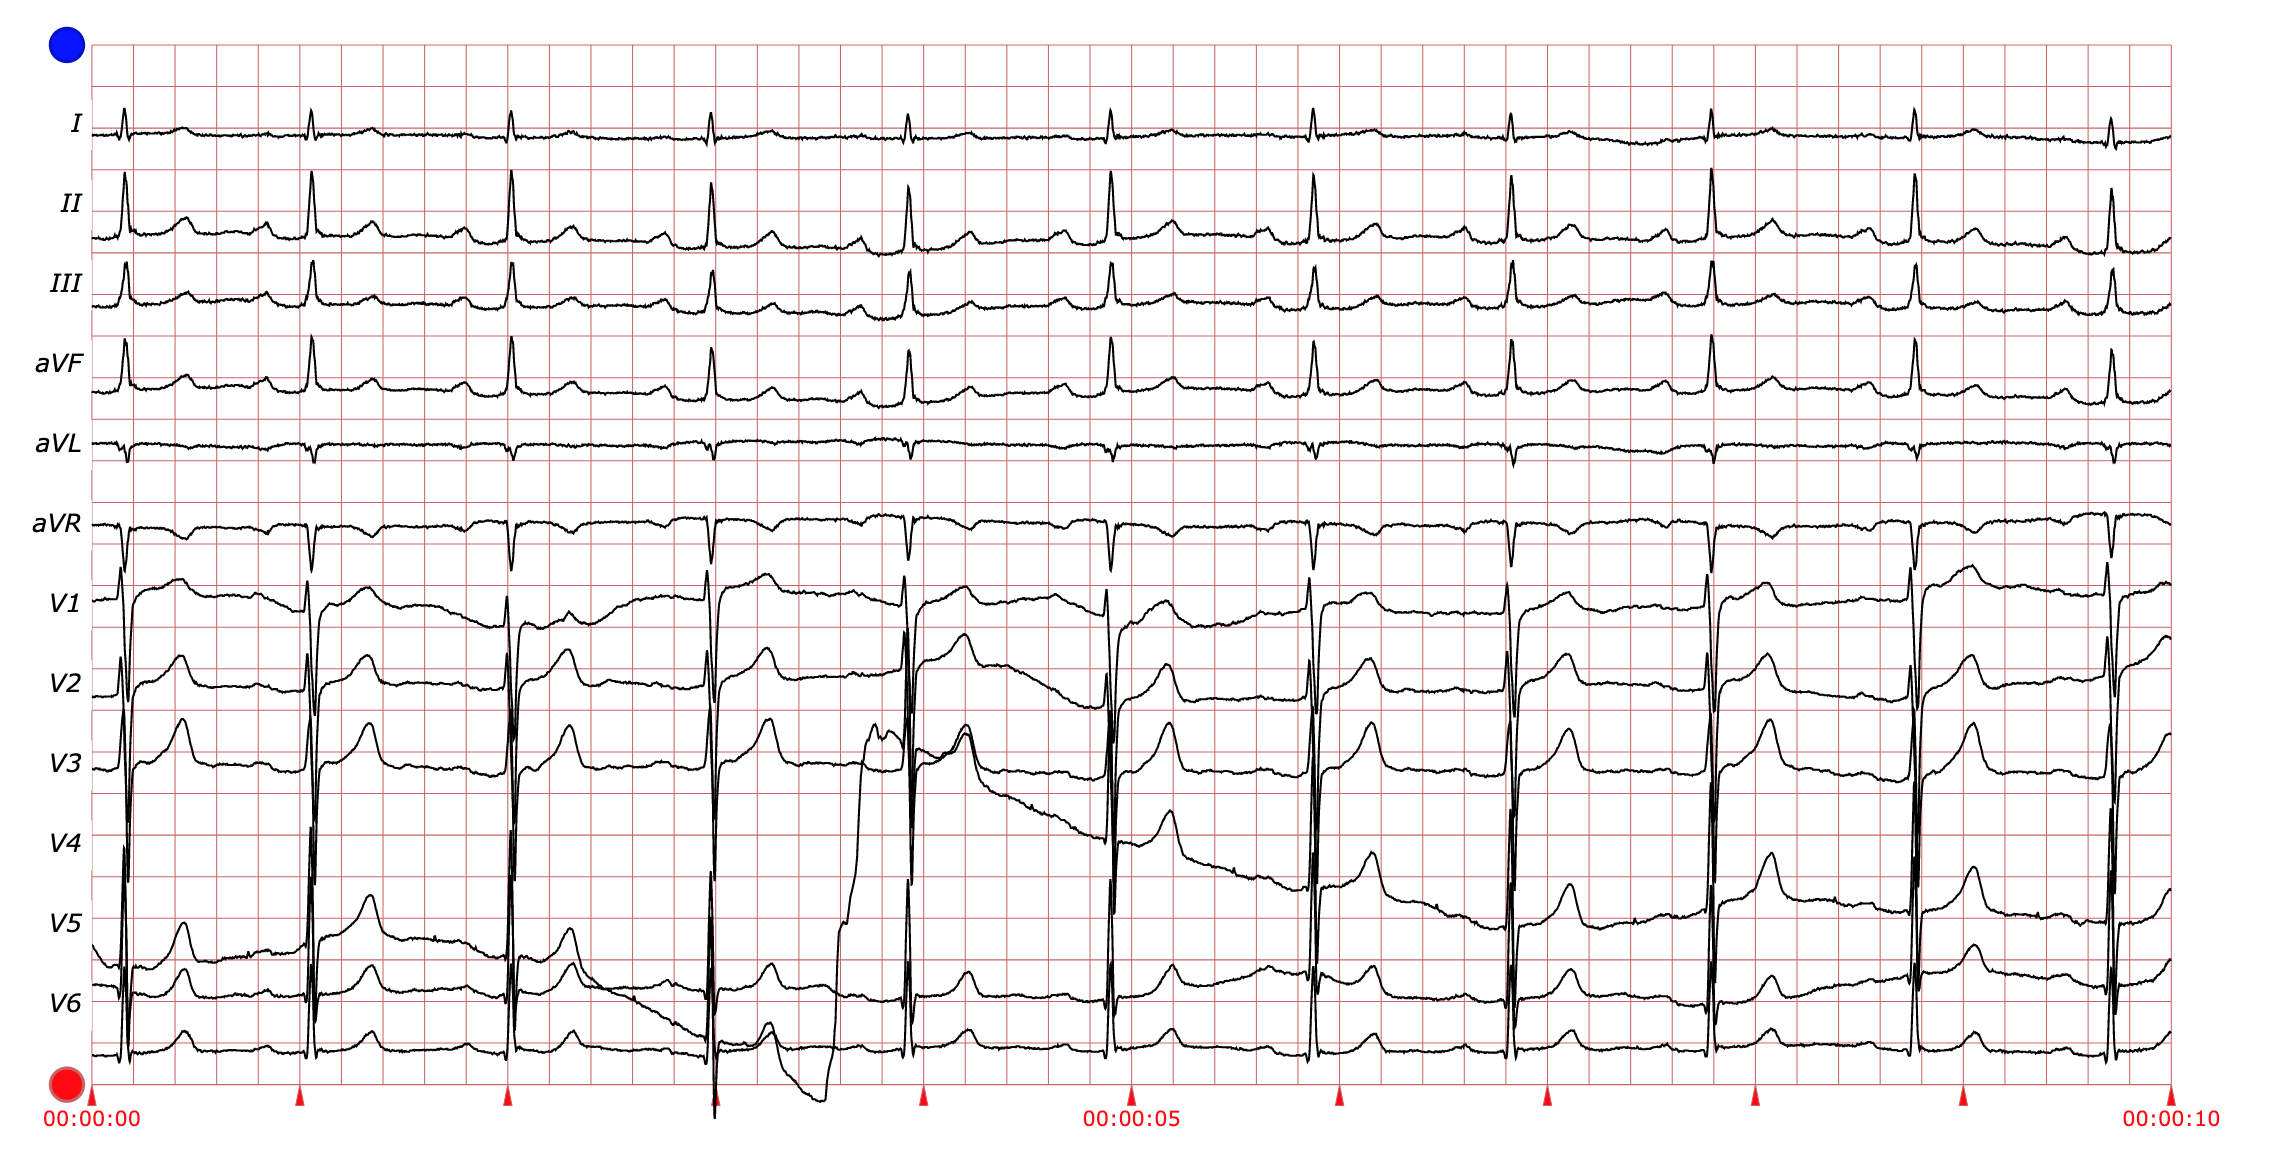

各类别心电信号图例

其他-心室预激(Others-VPE)

Others-VPE